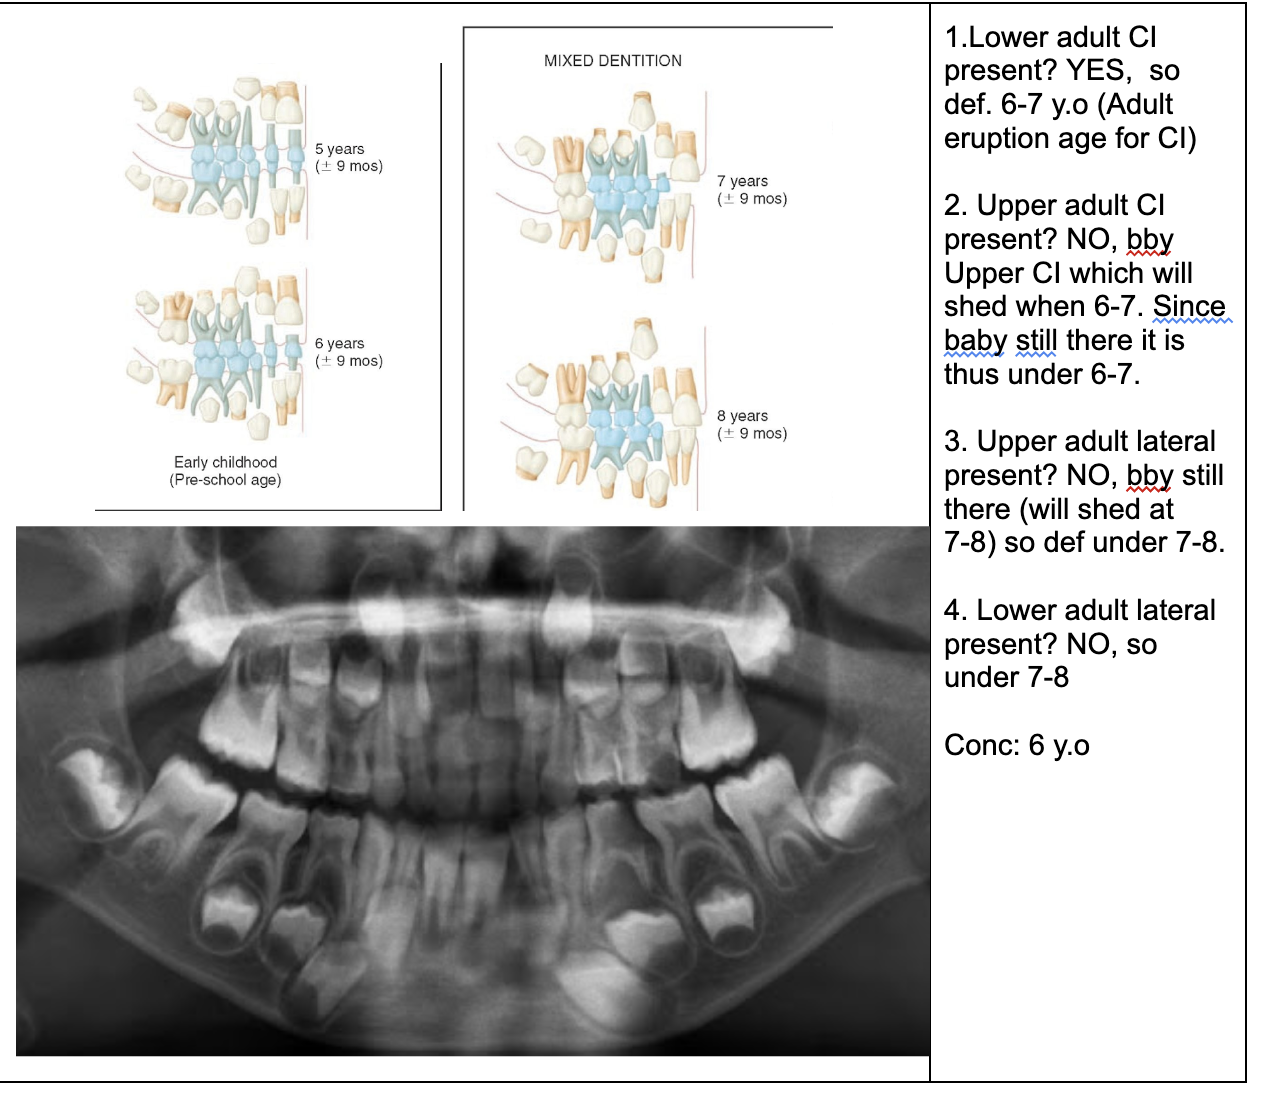

1.Ad. LOWER central incisors present? Yes. definitely 6-7 or older

1. Ad. UPPER CI present? Yes def. 7-8 y.o

3.Ad. Upper LAT incisor present (baby sheds 7-8)? NO so still under 7-8

Conc: pt is under 7